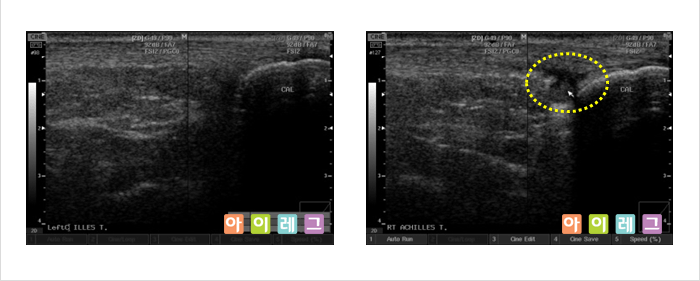

근골격계 초음파는 비전리 방사선의 한 종류인 초음파를 이용하여 영상을 만들어 냅니다. 초음파는

환자에 미치는 통증이나 방사선 노출이 전혀 없는 안전한 검사방법으로 관절,

연골, 인대, 건(힘줄), 점액낭, 근육, 신경 등 우리 몸을 움직이는 근골격계 구조물들의

이상(물이 차거나 염증 혹은 손상이 생긴 경우)을 진단하는 검사입니다. 환자의 진찰과

동시에 간편하게 시행할 수 있고, X-ray 등 방사선

검사로서 확인할 수 없는 경우 진단이나 치료에 도움이 됩니다.

또한, 근관절 정밀영상에 이용되는 고가의 MRI(자기공명영상)검사에 비해

저렴한 비용으로 시행할 수 있다는 장점이 있습니다.

* 위 영상은 모두 아이레그 의원에서 직접 검사한 영상 입니다.